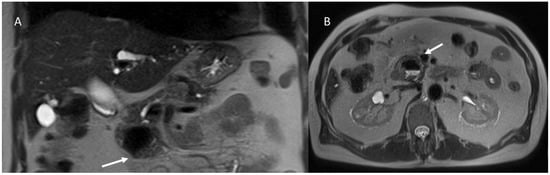

- Granata, V.; Fusco, R.M.; Catalano, O.; Filice, S.; Avallone, A.; Piccirillo, M.; Leongito, M.; Palaia, R.; Grassi, R.; Izzo, F.; et al. Uncommon neoplasms of the biliary tract: Radiological findings. Br. J. Radiol. 2017, 90, 20160561. [Google Scholar] [CrossRef] [PubMed]